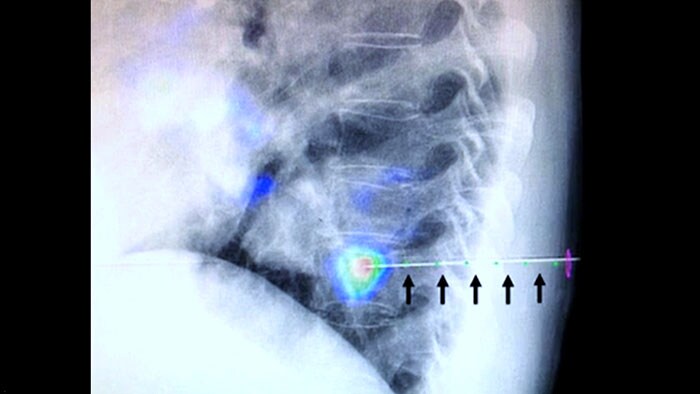

XperGuide Ablation* bietet umfassende Unterstützung bei der Behandlungsplanung und Echtzeit-Nadelnavigation. Die spezielle Parallaxenkorrektur ermöglicht die Planung von Nadelverläufen bei außermittigen Läsionen.1 Um eine möglichst gute Nadelposition für eine wirksame Ablation zu erreichen, zeigt dieses Tool den virtuellen Nadelverlauf an. Auch die Planung mehrerer Ablationsnadeln wird dadurch unterstützt. Außerdem werden Nadeleigenschaften wie Ablationszone/Isotherm angezeigt, damit die vollständige Tumorabdeckung vor der Ablation verifiziert werden kann.

Die perkutane Ablation (Hochfrequenz-, Mikrowellen- und Kryoablation) ist eine etablierte, minimal-invasive Behandlungsmethode für Nieren-, Leber-, Lungen- und Knochentumore. Dabei ist es besonders wichtig, den Tumor abzugrenzen und eine geeignete Anzahl an Nadeln und notwendigen Nadelverläufen festzulegen, damit der gesamte Tumor behandelt werden kann, ohne das umliegende Gewebe zu schädigen. Durch die präzise Navigation zur relevanten Läsion bei niedriger Strahlendosis und ohne Neupositionierung der Nadel werden die Erfolgschancen erhöht und das Komplikationsrisiko bei Biopsien und Ablationen reduziert. Der Endpunkt der Ablationsbehandlung kann mittels 3D-Bildgebung verifiziert werden, während sich der Patient noch auf dem Tisch befindet.

XperGuide bietet eine besonders präzise Live-Bildführung für jede Nadel zur Zielposition. Hierfür wird das Durchleuchtungsbild mit den vorab geplanten Bewegungsverläufen überlagert.3